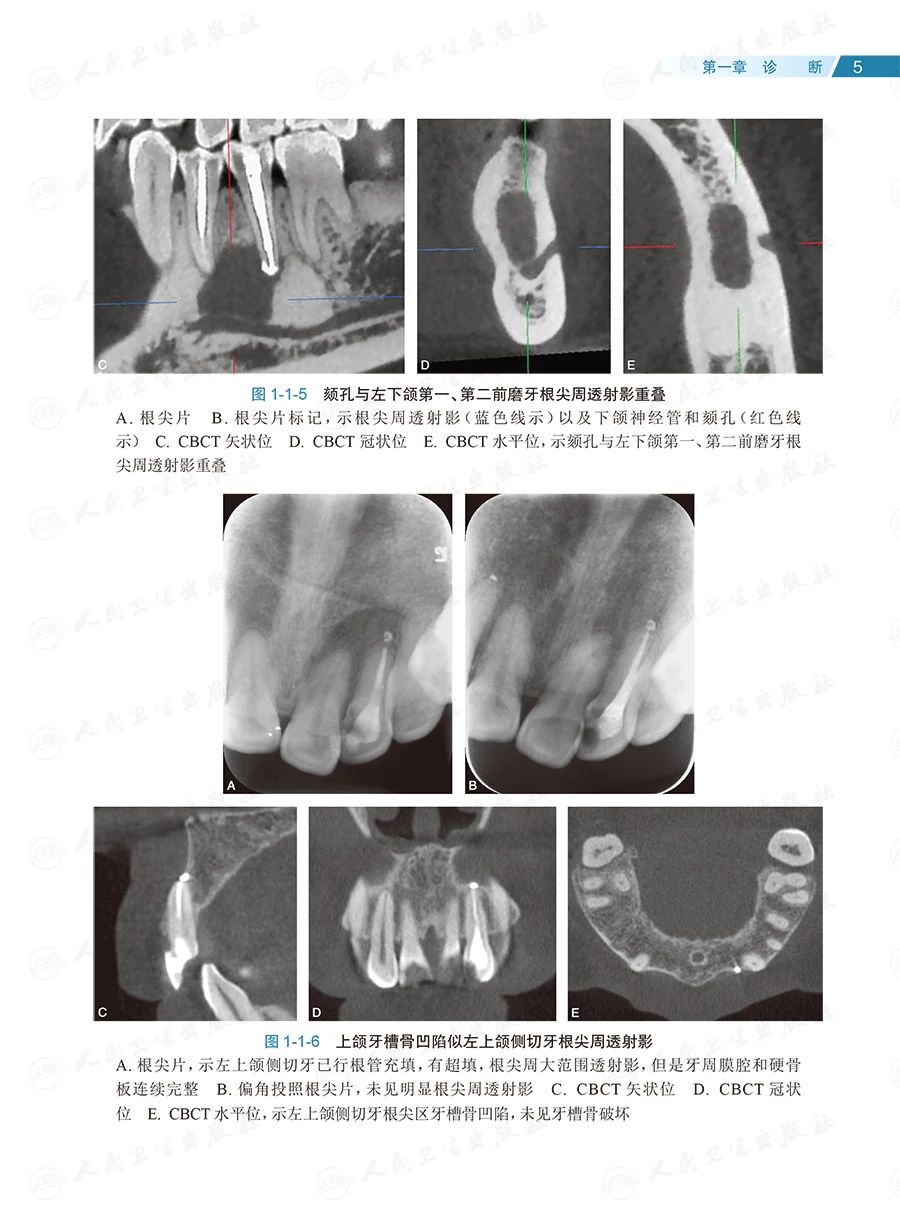

全书共133个临床病例、约1400幅照片,内容全面、图文并茂、形象直观。按照诊断、确定治疗方案和治疗的顺序,全书分为六章:第一章为诊断,主要讨论根尖周透射影、根裂的诊断和鉴别诊断;第二章为治疗方案选择,重点探讨非手术和手术(再)治疗方案的选择;第三章为在体手术治疗,即显微根尖外科,讨论特定牙位和牙根的手术,以及一些复杂疑难牙髓病、根尖周病的手术治疗;第四章为离体手术治疗,即显微意向再植术,全面讨论其适应证;第五章为多学科合作,包括牙髓源性上颌窦炎、联合应用引导性组织再生术(guided tissue regeneration,GTR)、自体牙移植术中的应用;第六章为全文总结,系统阐明牙髓病、根尖周病治疗的整体策略。